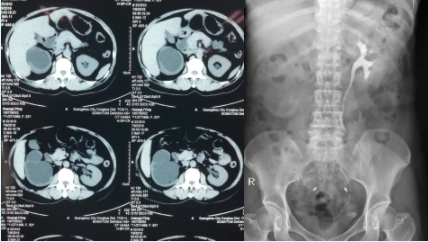

患者为中年女性,反复右侧腰腹部不适20年余,先后行2次右侧输尿管镜碎石取石术及3次输尿管切开取石和狭窄整形术。入院前6天再次出现右侧腰腹部不适,行尿路CT检测提示右肾重度积水,诊断为右侧输尿管狭窄并肾重度积水。患者因不堪忍受疾病折磨,入院后主动要求切除患侧输尿管及患肾。

李逊教授经仔细询问病史、查体及查看影像学资料后,认为虽然右肾重度积水,但是右肾实质仍较厚,仍有保留价值,建议先行右肾造瘘术,评估及保护右肾功能。行右肾造瘘术后,肾造瘘管每天引流出约1000ml尿液,并且留取肾造瘘管尿液检测提示尿比重等参数正常,提示右肾仍存在较好功能,值得保留。

患者术前CT及静脉泌尿系造影资料